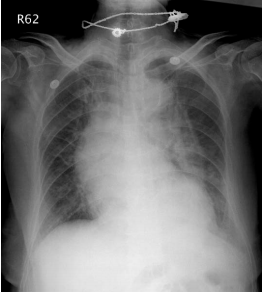

3. 82歲老婦人到院主訴五天來有日趨嚴重的呼吸困難。病史顯示30年前就有醫師告知心臟雜音,因無症狀,未曾有任何治療。近五年來運動耐受逐漸不佳,且偶有突發性悸動及心絞痛,特別在步行樓梯間更加惡化。住院當日清晨3點突然重度呼吸困難,因而急診住院。理學檢查:血壓110/62 mmHg;心跳90/分;頸靜脈怒張。心臟大小正常,但在右上胸骨緣及心尖部有Gr III/VI systolic murmur, S2減輕:其他所見尚無異常。其胸部X光、心臟超音波及心電圖如圖。WBC,5.2 k/micro L;AST,21U/L;CK,111U/L;CK-MB,14.6U/L;Troponin I,0.06 ng/ml。請問下列何項處置最恰當? (A) Percutaneous coronary intervention (B) Aortic valve replacement (C) Nitroglycerin IV infusion at the rate of 15mcg/min (D) Titrate PO carvedilol starting from 3.125 mg and reassess in 3 months (E) Treating with IV digoxin 0.125mg in conjunction with IV bolus Furosemide 20mg and then 20 mg BID

心電圖